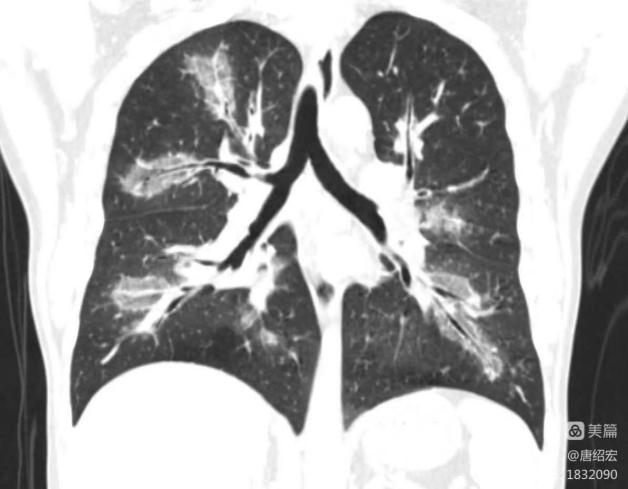

- 反晕征病灶沿气管血管束分布,能分清是沿肺动脉分布?还是沿支气管分布?

临床上围绕血管的渗出非常容易形成反晕征(上图红色箭头),而支气管的渗出不形成反晕征(上图蓝色箭头看似反晕征的中心是支气管,实际上是影像层面显示的原因,肺动脉没有显示出来)。

影像上三种表现形式:1. 单纯的血管侵袭可以出现反晕征(如本例),血管截断征、空洞及实变(但本例未出现);2. 单纯的支气管肺侵袭,出现树芽征(主要特征),磨玻璃影及沿支气管的实变;3. 同时有血管、支气管肺侵袭。